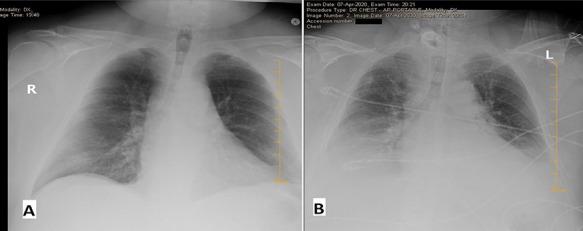

In this case report, we present a novel presentation of acute epiglottitis in a patient with severe acute respiratory syndrome-coronavirus 2 (SARS-CoV-2) who presented to the emergency room in extremis and respiratory failure requiring emergent cricothyrotomy. Epiglottitis has become less common since the introduction and widespread use of the type B (Hib) vaccine. This reduction in cases has shifted demographics of the disease from the pediatric population towards adults with comorbid conditions. Interestingly there is a high degree of overlap between many of the comorbidities between epiglottitis and COVID-19. The novel severe acute respiratory syndrome-coronavirus 2 (SARS-CoV-2), also referred to as coronavirus disease 19 (COVID-19), has been reported to affect the gastrointestinal tract and neural tissue and has been implicated in necrotizing encephalitis. We report the first known case of the novel SARS-CoV-2 virus presenting with acute epiglottitis.